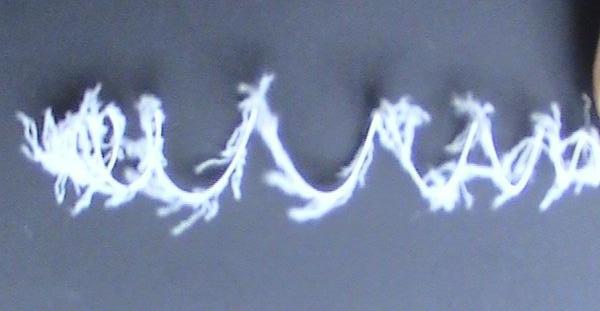

可控式弹簧栓子

除了Cookgroup 公司以外,Boston scientific公司也发展了自己的弹簧栓子血管栓塞系统。包括Interlock™ -35和Interlock™ -18。栓子导丝全长带有纤毛,不同于其它可推式Gianturco 弹簧栓子,该产品是可控的,即当弹簧栓子放置的位置完全合适的时候,才控制脱开释放。一旦认为不合适,或栓子释放的位置不理想可以回收重新释放,减少误放的潜在可能。它的主要危险是,过早地脱开释放,释放过程中被拆散(unraveling)以及并不是所有的栓子回收时顺利。

可脱式弹簧栓子

可脱性弹簧栓子

|

|

|

|

|

目前这种可脱式带有纤毛的弹簧栓子 |

这种弹簧栓子重要用于周围血管疾病的大的囊性动脉瘤的填塞;锚定大的高流量的动静脉畸形的滋养动脉;阻塞与重要动脉分支短段血管;血管解剖不能确定释放时导管能否稳定以及任何需要控制性释放的其它情况。其它也可以考虑的情况包括靶血管大于颅内血管的时候,周围血管动脉瘤囊为宽颈,“生手”需要许多弹簧栓子的病变和需要简单快速释放系统的病变。应该还有更多更好的理由会使很多人喜欢可脱式带有纤毛的弹簧栓子。

“If you remember, I did mention possible side-effects” 这句话道出了这种弹簧栓子的优点。其它的优点详见《厂家介绍 》